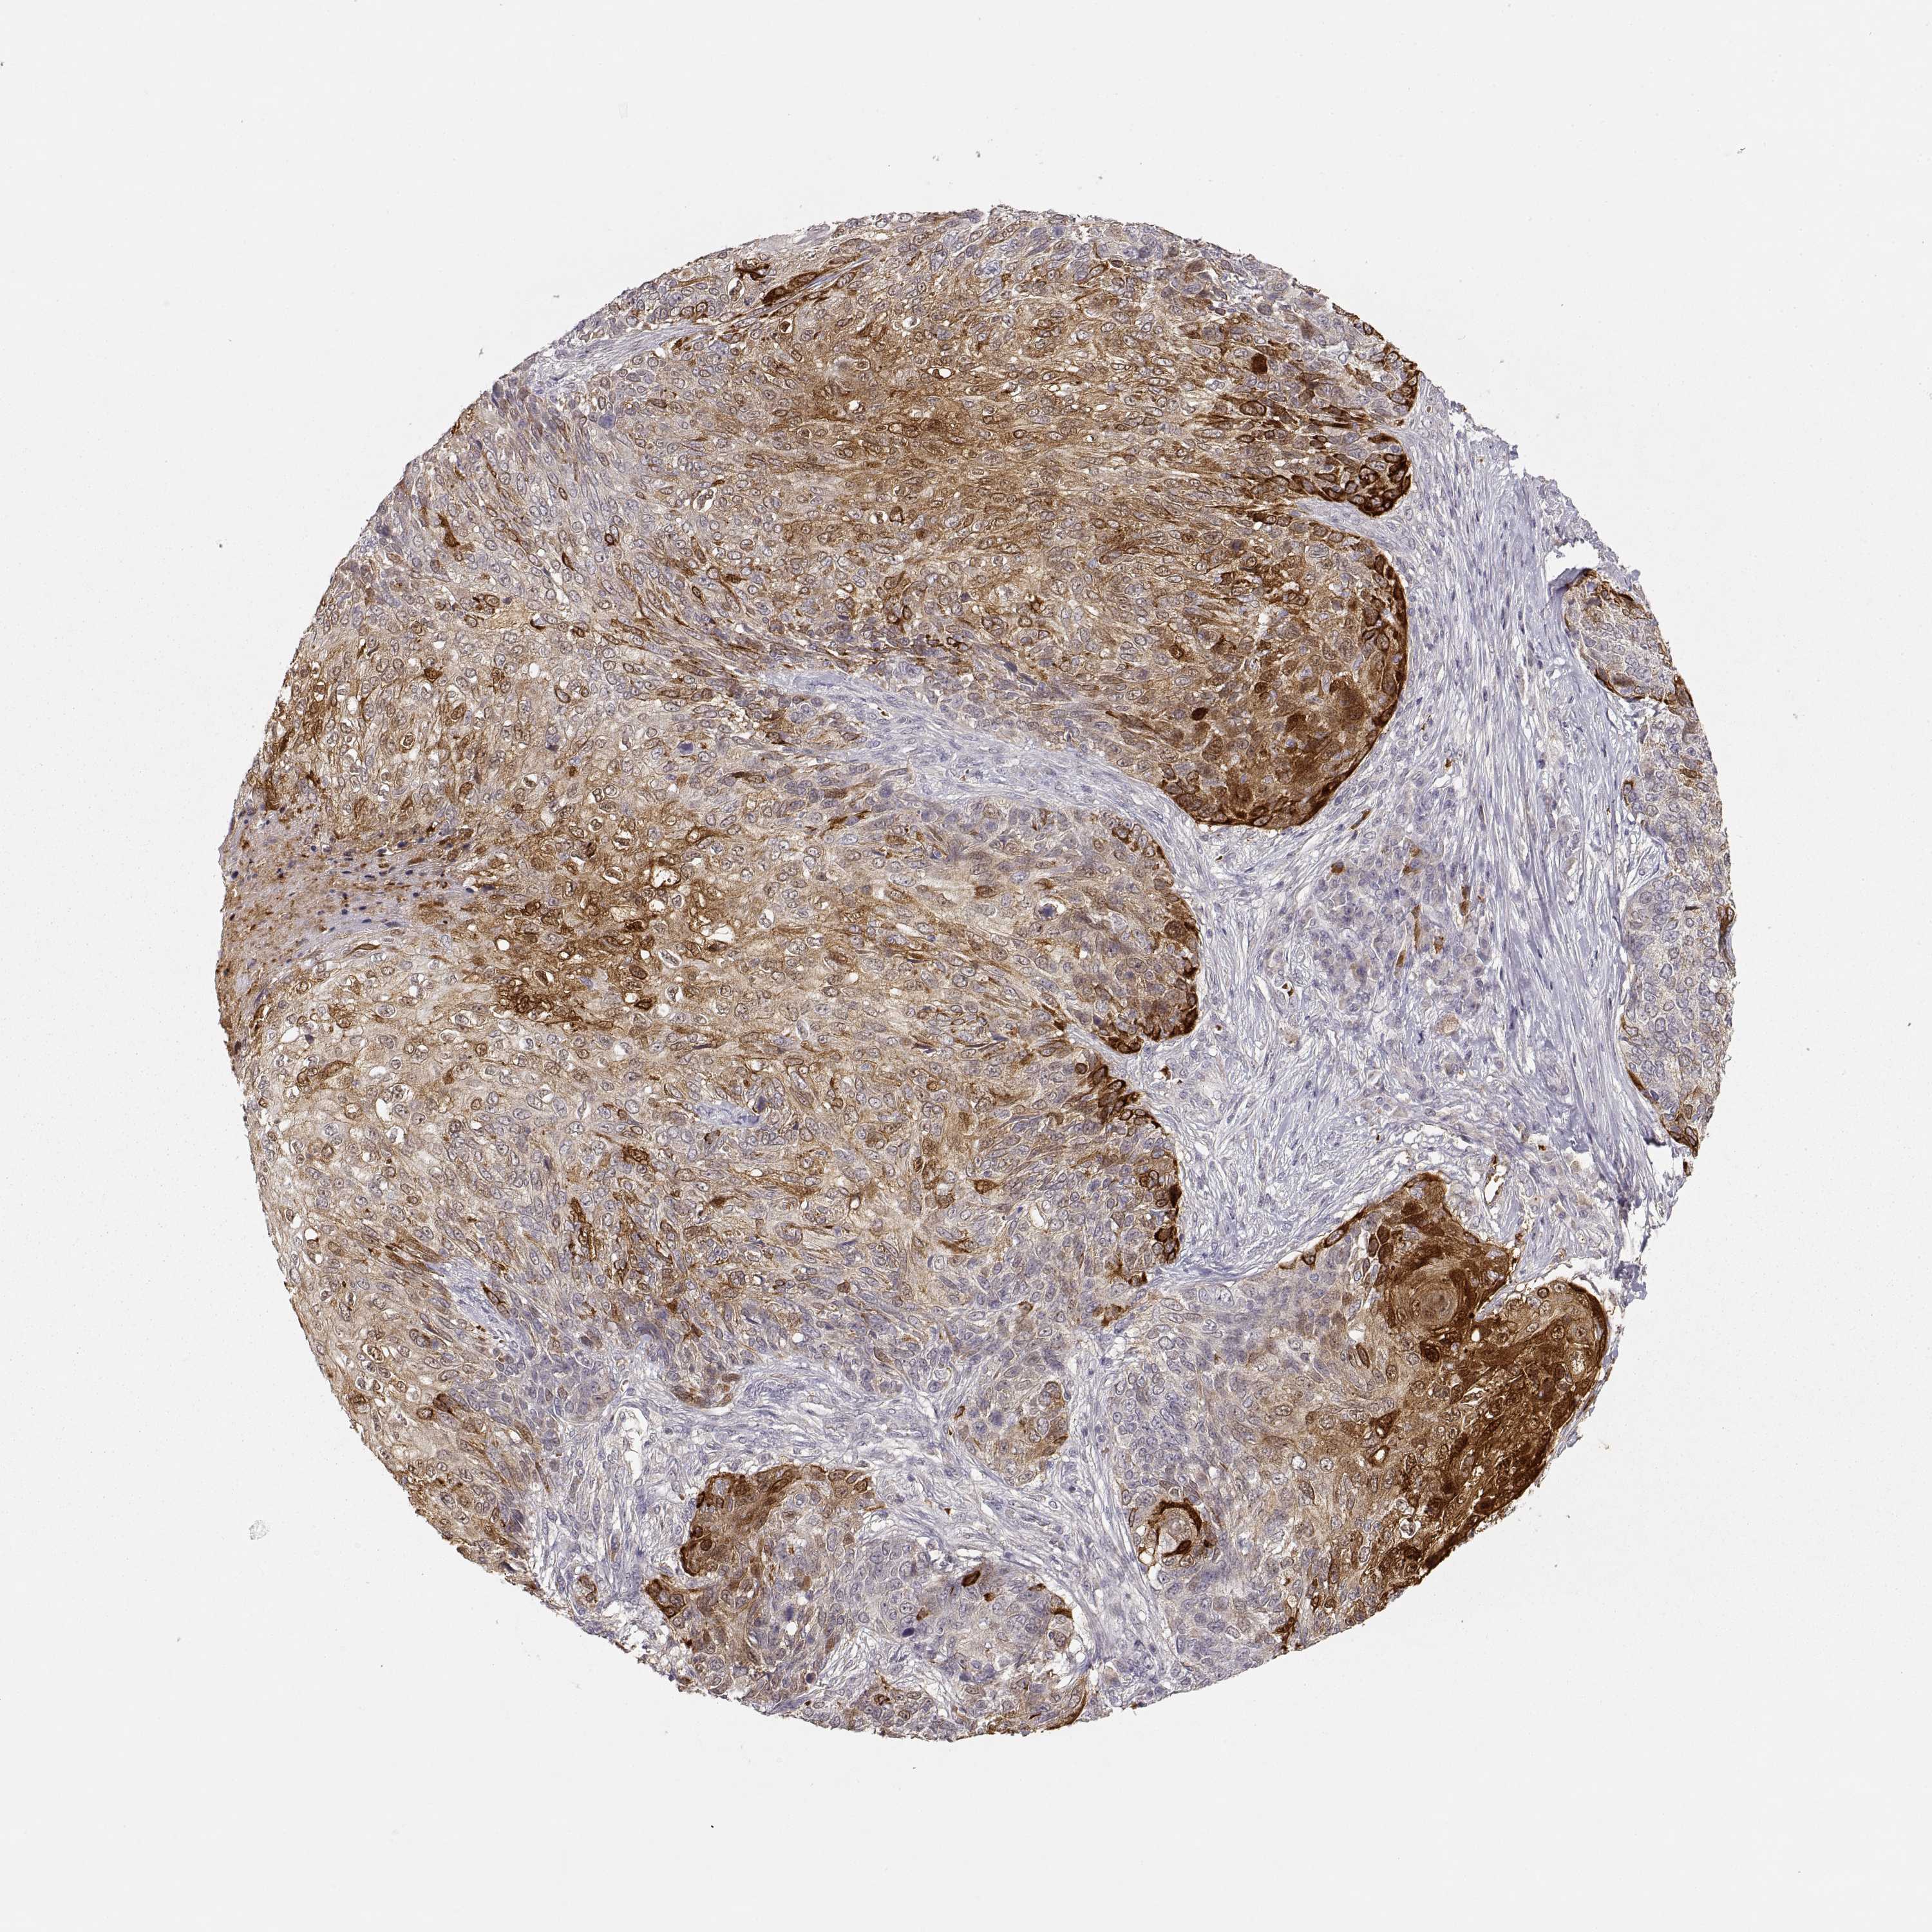

Basal cell and squamous cell cancer

SKIN CANCER - Protein expressioni

A mouse-over function shows sample information and annotation data. Click on an image to view it in a full screen mode. Samples can be filtered based on level of antibody staining by selecting one or several of the following categories: high, medium, low and not detected. The assay and annotation is described here.

Antibody stainingi

Antibody staining in the annotated cell types in the current human tissue is reported as not detected, low, medium, or high, based on conventional immunohistochemistry profiling in selected tissues. This score is based on the combination of the staining intensity and fraction of stained cells.

Each image is clickable and will lead to virtual microscopy that enables deeper exploration of all samples and also displays staining intensity scores, fraction scores and subcellular localization as well as patient and tissue information for each sample.

Antibody CAB004257

Antibody CAB078165

Staining

High

Basal cell carcinoma

Squamous cell carcinoma, NOS